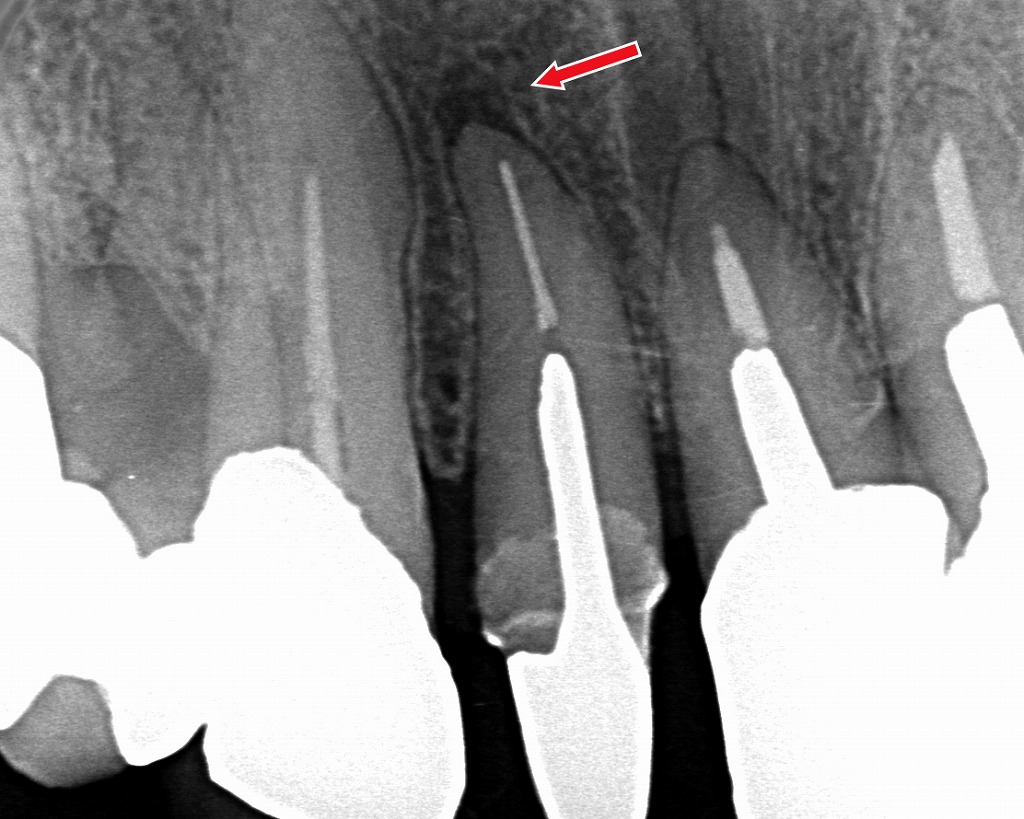

🔥 根尖病変(神経の炎症)

虫歯が進行して神経に炎症が起こると、歯の根の周囲に炎症が広がり浮いたように感じます。

赤い矢印が示すのは、上顎4番の根の先にみられる根尖病巣です。根の先で細菌感染や炎症が進むと、歯が押し上げられるような「浮いた感じ」や噛むと響く不快感が生じます。これは根尖部の炎症によって歯周組織の圧が高まり、歯がわずかに動揺するために起こる症状です。適切な根管治療で感染源を取り除くことが、症状改善のカギとなります。